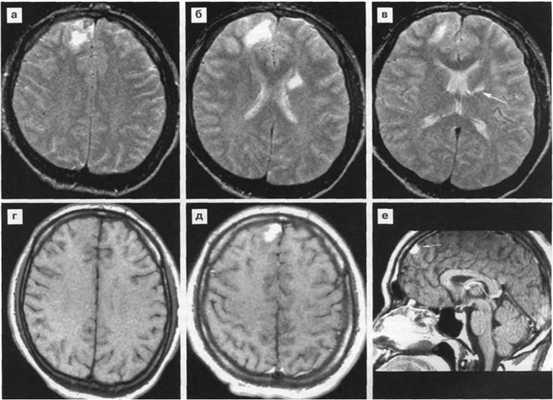

МРТ картина:

относительно симметричные диффузные или мультифокальные гиперинтенсивные изменения белого вещества в перивентрикулярной области и семиовальном центре с неровными краями, без масс-эффекта, не накапливающие контраст, либо более мелкие асимметричные очаги в белом веществе и базальных ядрах.

а-аксиальная КТ головного мозга

б,в,г -аксиальные МРТ в режимах Т2, Т1

аксиальная Т1 с контрастным усилением